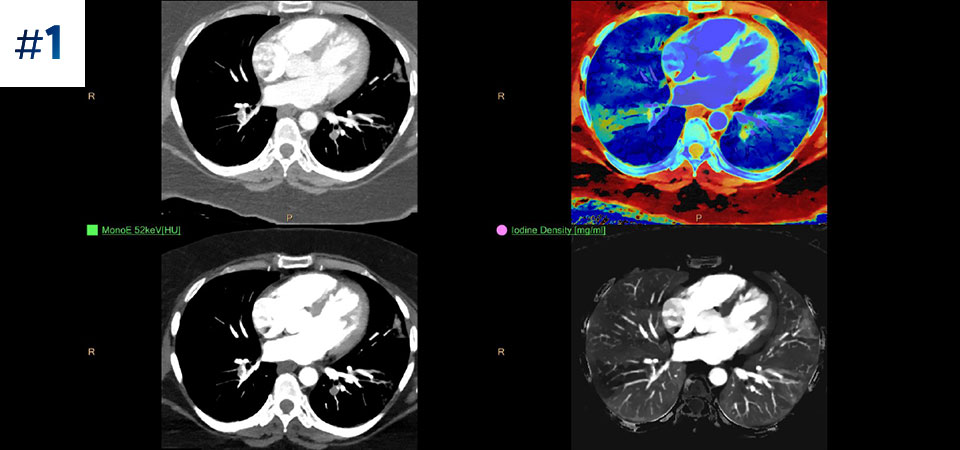

Получение результата спектральной КТ в самых разнообразных случаях Использование спектральных данных для широкого круга пациентов и получение результатов высокой точности различной сложности. Двухэнергетическая КТ позволяет избежать неинформативных результатов исследований, а значит многократно сократить время постановки диагноза. Благодаря повышению надежности диагностики вы получаете возможность предоставлять пациентам более качественную медицинскую помощь.

Брюшная полость ребенка